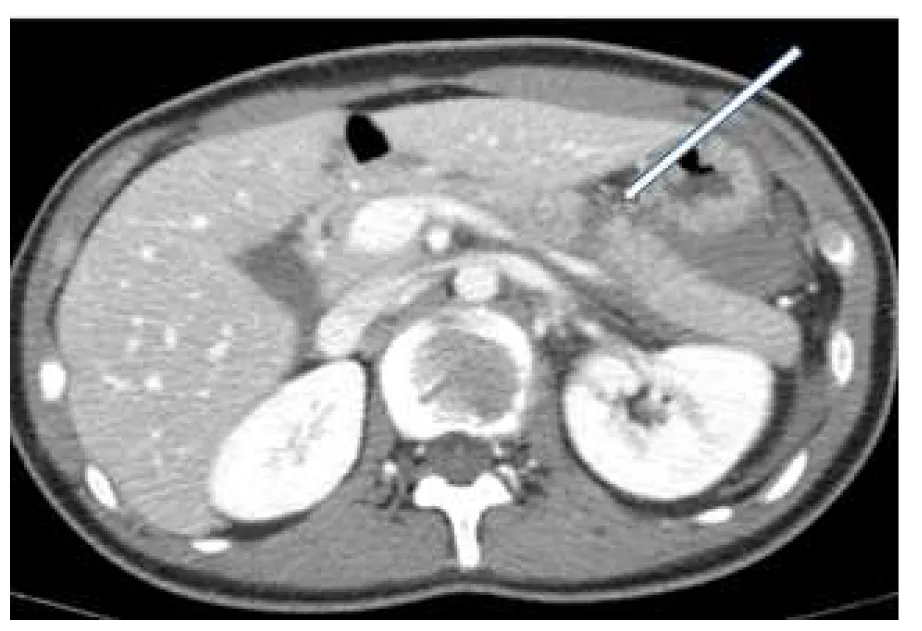

詳解

破題關鍵

這道題的解題核心在於辨識腹部電腦斷層影像中,箭頭所指的胰臟實質斷裂與周圍液體堆積,這是典型的胰臟撕裂傷表現。

選項拆解

登入查看完整詳解與互動作答